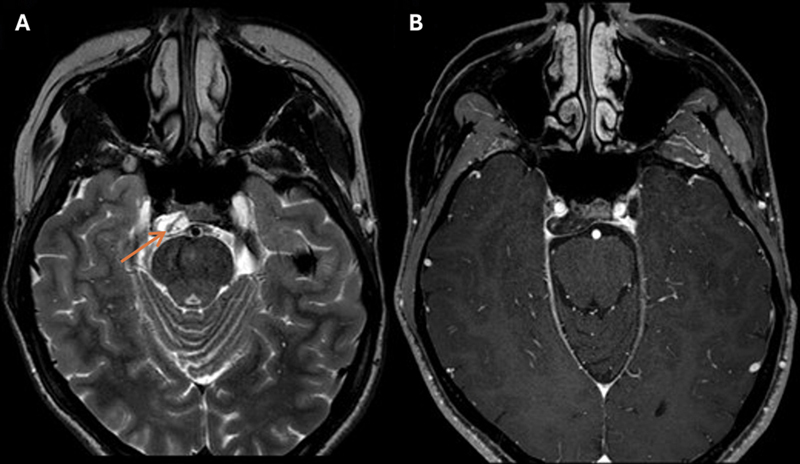

Case description: A 23-year-old woman presented with right abducens nerve palsy. Computed tomography and magnetic resonance imaging (MRI) revealed an off-midline petroclival lesion compressing the abducens nerve with characteristics of a chondrosarcoma. Preoperative MRI indicated spontaneous lesion regression, and the abducens nerve showed clinical improvement. Hence, the planned surgery was canceled. During the wait-and-scan period, abducens nerve palsy recurred. MRI confirmed lesion growth and showed an intratumoral linear structure indicative of blood. Even though preoperative MRI again demonstrated shrinkage, the lesion was surgically removed. Despite the unusual presentation, histopathological examination diagnosed a conventional chordoma. A second surgery was required to remove the residual tumor, after which the patient received high-dose photon beam therapy.